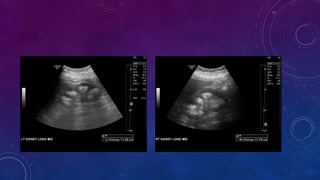

CYSTIC RENAL DISEASE

PRE TRANSPLANT

EVALUATION

PRE RENAL TRANSPLANT EVALUATION.